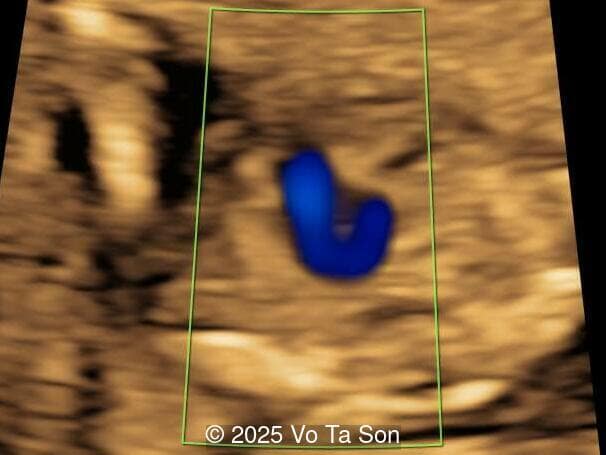

A woman underwent routine prenatal screening at 13 weeks. The non-invasive prenatal test (NIPT) showed low risk for common aneuploidies including trisomy 21, 18, and 13. However, first-trimester anomaly scan revealed multiple fetal anomalies.

We present a case of Triploidy with a 69,XXY chromosomal complement and open spina bifida in the first trimester.

Our imaging revealed the following significant fetal abnormalities:

• Ventricular septal defect (VSD)

• Tricuspid valve regurgitation

• Right aortic arch